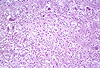

CASO N° 3 (Dr. Abel e Dr. Delgado)

Paciente do gênero masculino, 21 anos de idade, apresenta uma lesão no palato duro.